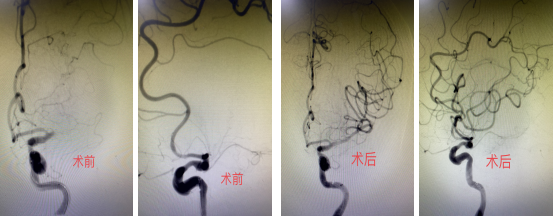

在介入手术室中,紧张而庄严的氛围弥漫开来。医护人员们全神贯注,与时间赛跑,每一个动作都至关重要。手术进程中,造影图像清晰地显示了患者左侧大脑中动脉M1段远端发生了闭塞,这正是导致此次病发的“罪魁祸首”。在宝贵的机械取栓时间窗内,王虎清主任医师带领团队经过一系列紧张有序的操作后,成功地将血栓抽拉出来,并紧接着进行了球囊扩张及支架置入术,使闭塞的血管重新再通。这场生命与时间的较量,神经内科介入团队凭借高超的技术与默契的协作,最终成功将患者从死神手中夺回。

术前术后左侧大脑中动脉对比,术后患者左侧大脑中动脉再通